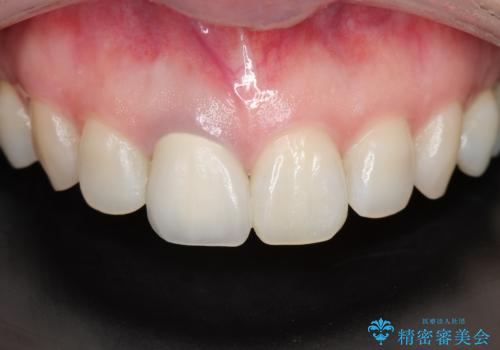

最新の症例

Latest cases